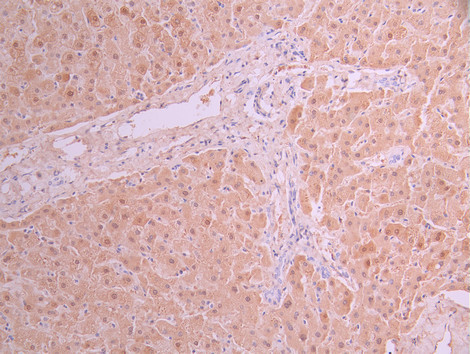

IHC image of CSB-RA290314A0HU diluted at 1:100 and staining in paraffin-embedded human liver cancer performed on a Leica BondTM system. After dewaxing and hydration, antigen retrieval was mediated by high pressure in a citrate buffer (pH 6.0). Section was blocked with 10% normal goat serum 30min at RT. Then primary antibody (1% BSA) was incubated at 4°C overnight. The primary is detected by a Goat anti-rabbit polymer IgG labeled by HRP and visualized using 0.05% DAB.

IHC image of CSB-RA290314A0HU diluted at 1:100 and staining in paraffin-embedded human liver tissue performed on a Leica BondTM system. After dewaxing and hydration, antigen retrieval was mediated by high pressure in a citrate buffer (pH 6.0). Section was blocked with 10% normal goat serum 30min at RT. Then primary antibody (1% BSA) was incubated at 4°C overnight. The primary is detected by a Goat anti-rabbit polymer IgG labeled by HRP and visualized using 0.05% DAB.